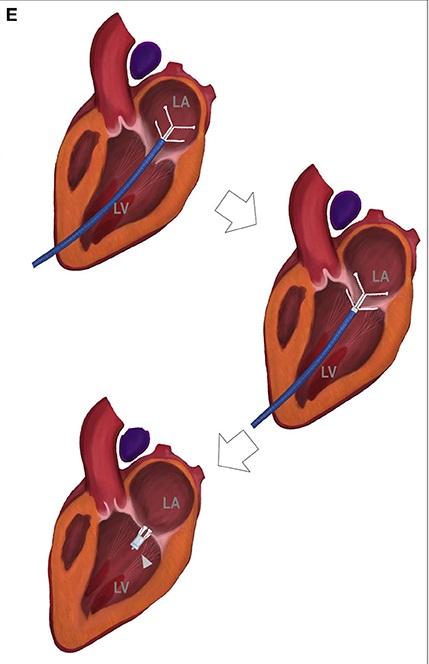

Bei der V-Clamp (oder TEER: Transcatheter edge-to-edge mitral valve repair)-Technik wird über einen Herzkatheter ein kleines Implantat ins Herz gebracht, welches über einen Klammermechanismus die beiden Mitralklappen gegeneinander zieht, somit die Öffnung vom Ventrikel in den Vorhof verkleinert und damit den Blutrückfluss vermindert. Das System ist eine relativ neue Entwicklung, weshalb noch nicht sehr viele Daten zu der Wirksamkeit des Eingriffs vorliegen - erste Erfahrungen zeigen aber ein erfreuliches Bild bezüglich Operationsrisiken und längerfristiger Prognose.